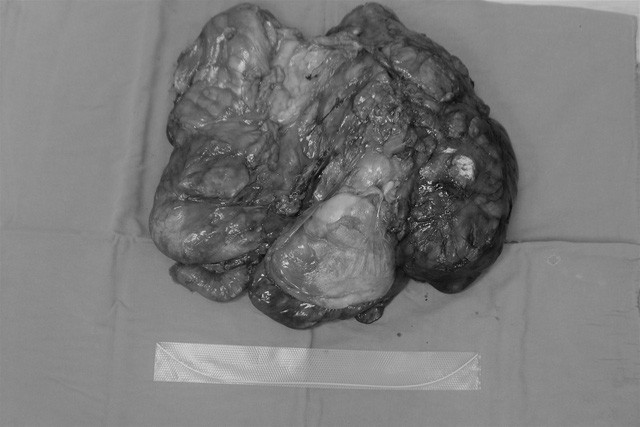

| Phim chụp khối u |

Anh Chu Văn Th. (46 tuổi) trú tại Sơn Tây, Hà Nội đến thăm khám tại bệnh viện K trong tình trạng đau bụng kéo dài 6 tháng, ăn uống vào thấy đầy bụng, khó tiêu. Kết quả chụp chiếu ổ bụng thấy có khối u kích thước “khủng” 40x35x38 cm, u chiếm hoàn toàn nửa bụng bên trái và phần giữa ổ bụng. Bác sĩ khoa Ngoại bụng 1 chẩn đoán là u mạc treo và cần phẫu thuật loại bỏ khối u.

Đánh giá đây là ca bệnh rất khó vì u rất to và vấn đề đặt ra cho các bác sĩ khoa Ngoại bụng 1 là khối u ở vị trí “hiểm”. Khối u đẩy toàn bộ các quai ruột sang phải và đẩy các tạng ổ bụng ra phía sau, đè đẩy vào động mạch chủ bụng, tĩnh mạch chủ dưới, khối u được cấp máu bởi động mạch tách ra từ động mạch chủ bụng và động mạch mạc treo tràng dưới, đè đẩy vào thận trái và lách.